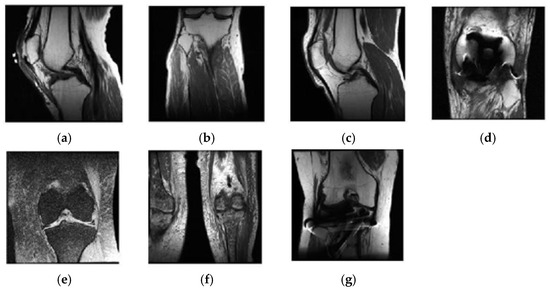

2.3. Selecting Eligible Data

2.3.1. Classification of Sagittal Images and Results

2.3.2. Classification of Coronal Images and Results

2.3.3. Classification of Axial Images and Results